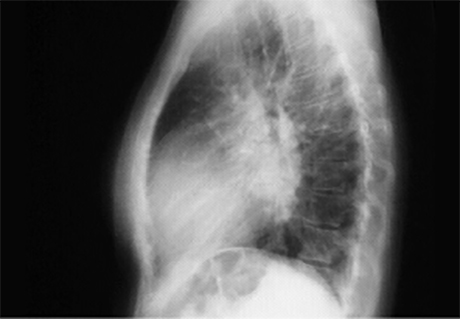

In the lateral view,

left atrial enlargement is further reflected by the prominent posterior left atrial shadow. Right ventricular enlargement is best seen in this view and is manifested by obliteration of the retrosternal air space.